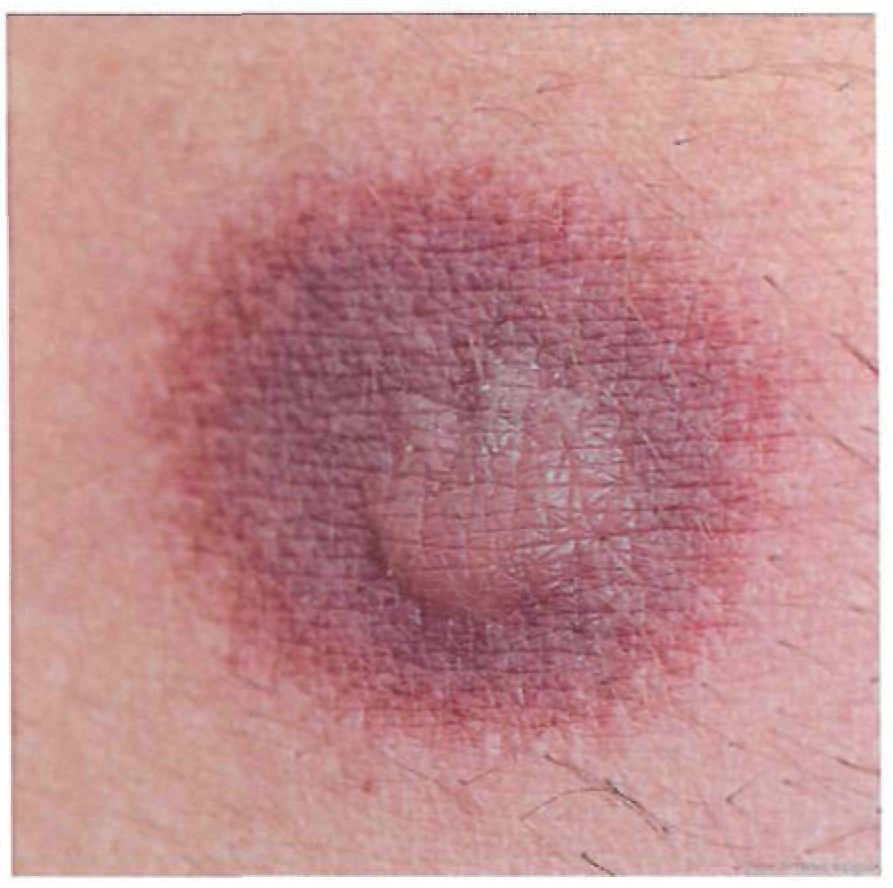

Период высыпаний

На 3-4-й день болезни температура тела снижается до субфебрильной, одновременно на коже головы (прежде всего на лице) и на слизистых оболочках полости рта, гениталий, конъюнктивы, роговицы глаз появляются необильные элементы сыпи. Энантема на слизистых оболочках полости рта обычно предшествует появлению экзантемы. Первые элементы сыпи обычно появляются на лице, быстро распространяясь на верхние конечности, а затем - на туловище и нижние конечности, поражая ладони и подошвы. Распространение экзантемы имеет центробежный характер - на туловище элементов меньше, чем на лице и конечностях.

Высыпания эволюционируют через стадии:

- макула (пятно) (1-2 дня);

- папула (узелок) (1-2 дня);

- везикула (пузырек, заполненный прозрачной жидкостью) (1-2 дня);

- пустула (гнойничок) с пупковидным вдавлением в центре (5-7 дней);

- корочка (7-14 дней).

В 70-80% случаев сыпь характеризуется мономорфностью, в остальных случаях может отмечаться полиморфизм [38]. На одном участке кожи сыпь всегда мономорфна.

В 95% случаев сыпь поражает лицо, в 75% - ладони и подошвы, что является отличительным признаком заболевания. Также поражаются слизистые оболочки полости рта (в 70% случаев), половые органы (30%), конъюнктива и/или роговица (20%). У части пациентов имеет место проктит с поражениями перианальной области изолированно или в сочетании с высыпаниями в области гениталий [39]. Количество элементов сыпи варьирует от единичных до нескольких тысяч [13].

Согласно данным ВОЗ у многих пациентов с МРХ, выявленных в 2022 г. в неэндемичных по данному заболеванию странах, заболевание протекает в атипичной форме, включающей следующие признаки: появление небольшого количества элементов сыпи или только одного элемента, которые возникают в области гениталий или промежности и не распространяются на другие участки кожи; наличие очагов поражения кожи на разных (асинхронных) стадиях развития; появление сыпи до начала увеличения лимфатических узлов, лихорадки, недомогания или других симптомов [41].